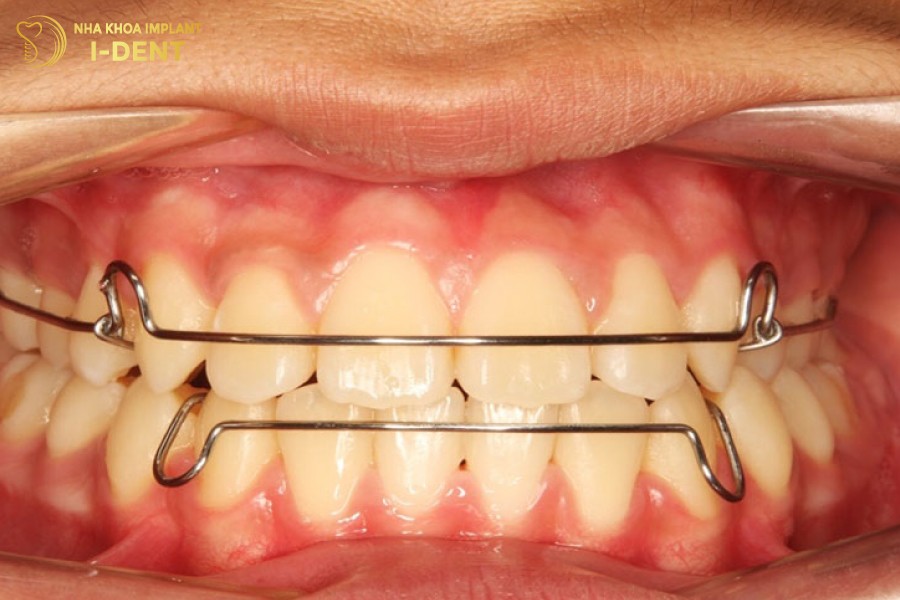

3.1. Sử dụng hàm duy trì

Bạn cần sử dụng hàm duy trì để khắc phục răng bị chạy sau khi niềng vì hàm duy trì là giải pháp quan trọng nhất giúp cố định răng và giữ răng ở đúng vị trí đã được sắp xếp ngăn răng dịch chuyển trở lại do lực co kéo tự nhiên của mô xương và mô mềm.

Đeo hàm duy trì đúng cách để giữ răng không bị dịch chuyển.

3.2 Đeo hàm duy trì đúng cách

Trường hợp răng chỉ mới chạy ít trong thời gian đầu sau khi tháo niềng thì bác sĩ sẽ lấy dấu mẫu hàm chế tác hàm duy trì để giữ răng về đúng vị trí và sớm ổn định trong xương hàm. Sau khi có hàm duy trì bệnh nhân cần đeo hàm liên tục 24 giờ đầu tiên để cố định răng, sau đó thời gian đeo sẽ được rút ngắn dần ở những giai đoạn tiếp theo, chuyển sang đeo buổi tối hoặc giảm tần suất do bác sĩ chỉ định cho đến khi răng đã cố định hoàn toàn và không còn dấu hiệu chạy răng.